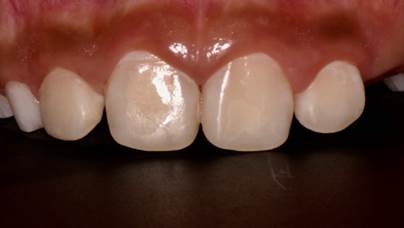

El examen dental se realizó en el consultorio odontológico bajo luz artificial. La clasificación de la FD se realizó de acuerdo con el criterio de Thylustrup y Fejerskov (1978) 5. Este índice permite registrar la FD basado en las características histopatológicas e incluye desde los estadios más leves hasta los más severos (escala ordinal de 0 hasta 9) (Cuadro 1). Considerando la pérdida de estructura, dientes con TF ≥ 5 fueron clasificados como FD severa. De esta manera, todos los incisivos anteriores superiores permanentes fueron clasificados con el código TF6 (superficie totalmente opaca, cuyas depresiones redondas se juntan con menos de 2mm de altura) (Figura 2). En el Cuadro 2 se presenta la lista de diagnósticos de la paciente.

Figura 2 Incisivos superiores permanentes con fluorosis dental (TF6). Las flechas muestran las pérdidas de estructura.